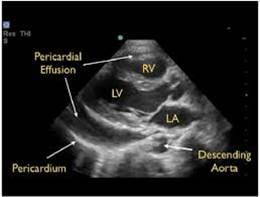

- Pericardial effusions are common and range from benign to life threatening.

- In contrast to an effusion, epicardial fat pads are isolate to the anterior of the heart and often have increased echogenicity.

- In the setting of trauma, significant effusion may signify cardiac injury.

- The parasternal long axis view can be helpful in distinguishing between pericardial (anterior to descending thoracic aorta) and pleural (posterior to the DTA) effusions.

- Findings of tamponade on echocardiography include right ventricular diastolic collapse, right atrial systolic collapse, plethoric IVC, and increased inflow variation.19

- Pericardial tamponade is potentially lethal without intervention. Intuitively POCUS can decrease time to intervention although to date this is supported only by weak evidence.20

- Epicardial fat pads are usually isolated to the anterior heart and have internal echoes. Pericardial fluid usually collects in the dependent posterior pericardial space and can be seen surrounding the myocardium anterior to the descending aorta. A left sided pleural effusion will be located posterior to the descending aorta.

- Figure 15. Parasternal long axis showing pericardial effusion anterior to descending thoracic aorta